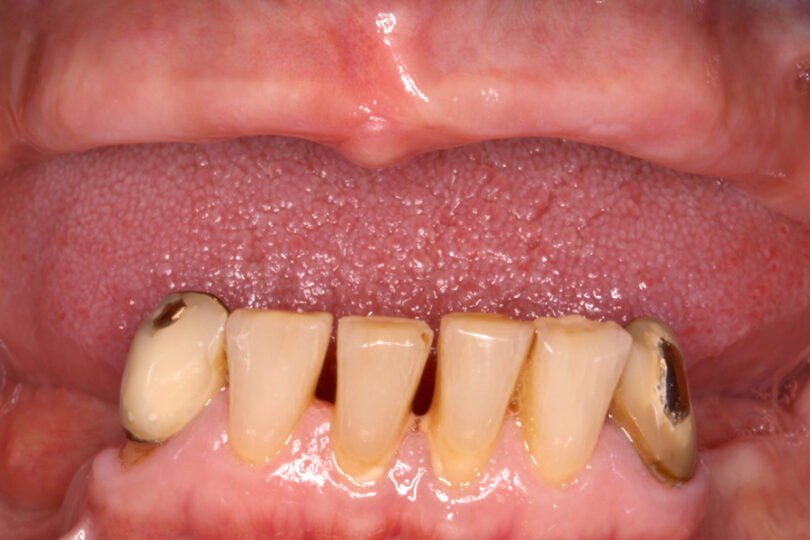

As seguintes imagens apresentam um dos casos incluídos no estudo (figura 03 – 15).